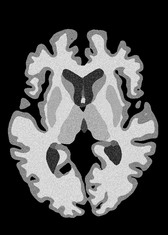

4.2 Registration to a 100 micron ex-vivo brain MRI volume

To showcase the efficacy of our method on real large scale images, we register a 250 in-vivo MRI image (Lüsebrink et al., 2017) to a 100 ex-vivo FLASH human brain volume (Edlow et al., 2019). This represents an inverse problem with more than 11.2B optimizable parameters (compared to 20M for clinical datasets), or 44.8GB of GPU memory. The entire problem does not fit on most GPUs, necessitating distributed multimodal registration. We optimize a composite transform - affine followed by a diffeomorphic mapping; details can be found in Section E.1. Multimodal deformable registration took 58 seconds on 8 NVIDIA A6000 GPUs, which is unprecedented at this resolution. Fig. 6 shows qualitative results, highlighting the ability to register highly detailed structures such as cerebellar white matter; these structures are not visible at macroscopic scales. The resultant advantages of performing registration at this scale can allow researchers to characterize the neuroanatomy at microscopic resolutions and allow morphometric analysis of cortical layers and subcortical nuclei among other structures.